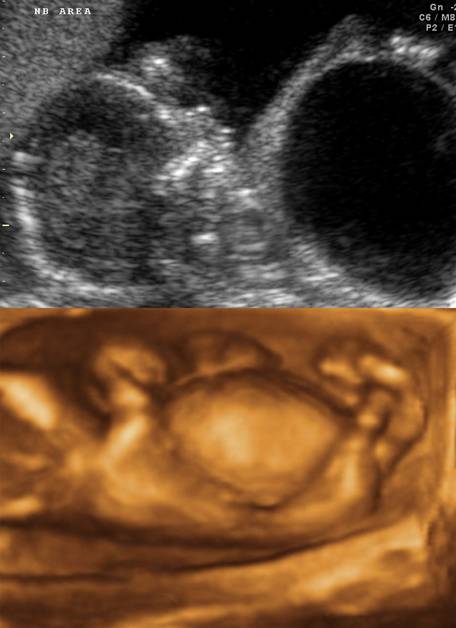

Fetal megacystis at 15 weeks of gestation.

Trisomy 18.

Note the clubbed hands.